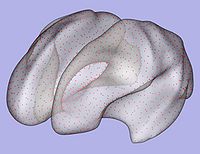

- 1.7. Genus zero cortical surface creation and inflation

- 1.7.1. Genus zero cortical image and surface creation

- Tool: GenusZeroImageFilter (UNC Slicer3 external module)

- 1.7.2. White matter surface inflation

- Iterative smoothing using relaxation operator (considering average vertex) and L2 norm of the mean curvature as a stopping criterion

- Iteration stopped if vertices that have too high curvature (some extremities)

- Tool: MeshInflation (UNC Slicer3 external module)